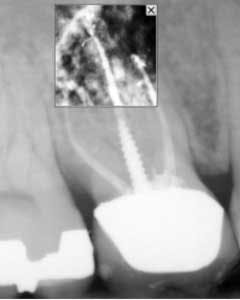

Once all of the canals are found, I will go through the series of Sybron Twisted Files size 25 tapering from 0.10 to 0.80 to 0.60 to 0.40. The 0.40 file should reach the working length for most canals. On a large palatal or distal canal, the 0.60 TF will usually reach working length. After which, using the crown-down technique with the Brasseler EndoSequence rotary files, instrument each canal until files reach the working length. Once instrumentation is complete, take a P.A. with gutta-percha to confirm instrumentation to working length. I find it much easier to take working length films with gutta-percha rather than files (which may fall out, bend, or separate)

- Separated file — The dreaded separated file is probably the most common complication clinicians encounter when performing root canals. There was a time when those broken instruments made me wish I never started the root canal in the first place. These days, I will work to bypass the file and get a predictable result.

To prevent file fractures, irrigate after every file. Also, apply gentle pressure and never push when instrumenting a canal.

If a file separates, take a P.A. film immediately to figure out where in the canal the file is lodged. Most likely there’s a curve that the file could not negotiate. Start negotiating the canal with a 6 or 8 C-file. The goal is to engage the space around the file where you can instrument next to it. It could take an extra 30 or 40 minutes and lots of irrigation, but you should be able to negotiate the canal with a 15 file to working length. Irrigate very well and obturate. Sometimes the file will actually exit the orifice of the tooth when irrigating. But it’s perfectly reasonable to use the file as part of the fill.